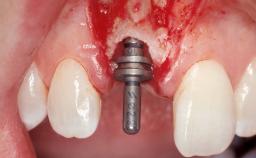

A 42-year-old female patient was referred to our clinic at the School of Dentistry of the University of São Paulo in November 2004, presenting a deficient restoration in the upper left central incisor. The clinical examination revealed no gingival retraction or any signs of gingival inflammation and, therefore, previous periodontal treatment was not considered. The patient presented a high lip line at full smile and a thin tissue biotype. This combination characterized a high-risk situation from an anatomic point of view, which required careful preoperative planning and cautious surgical execution.

Placement Protocol Immediate implant placement

Loading Protocol Immediate

Retention Screw-retained Screw-retained

Provisional Implant-Supported Prosthesis Prosthodontic margin < 3 mm apical to mucosal margin Prosthodontic margin < 3 mm apical to mucosal margin